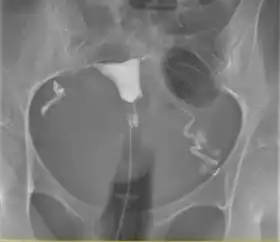

![]() A normal hysterosalpingogram. Note the catheter entering at the bottom of the screen, and the contrast medium filling the uterine cavity (small triangle in the center). | |